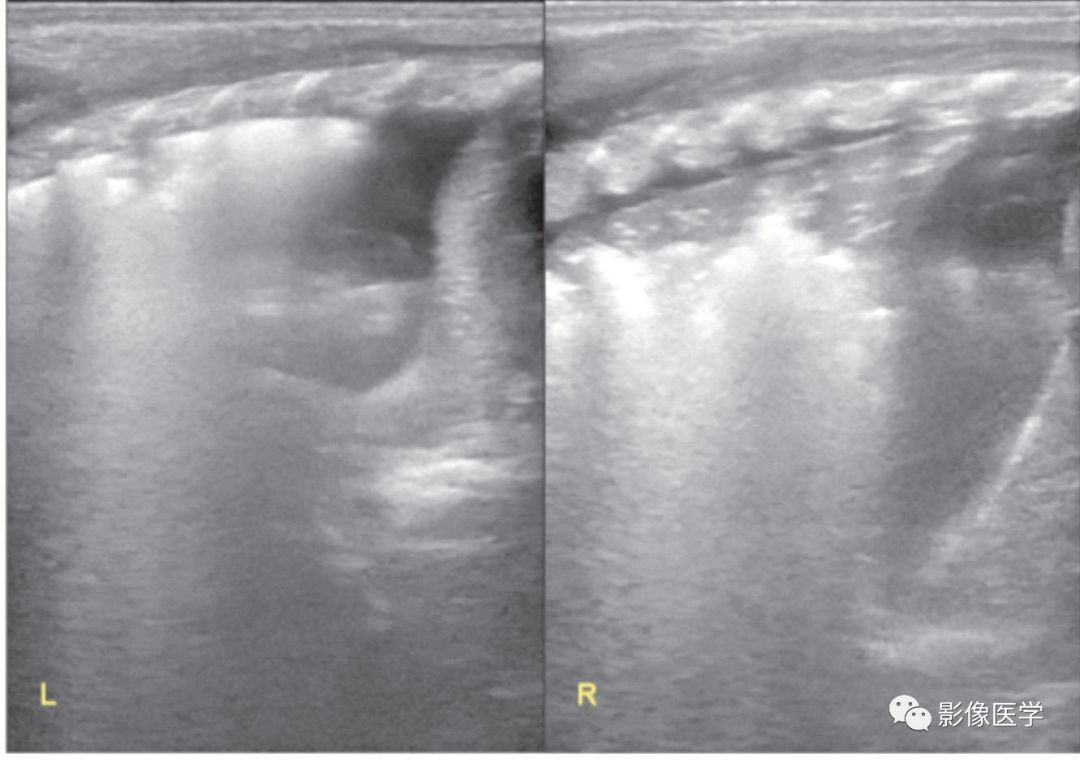

图6-3 重症感染性肺炎(2)

胎龄32+6周,出生体重2 400g。出生后7d,呼吸困难,胸部X线检查结果符合新生儿肺炎改变。肺脏超声显示双肺大面积肺实变伴支气管充气征,实变区边缘不规则,胸膜线模糊或消失,A线消失。